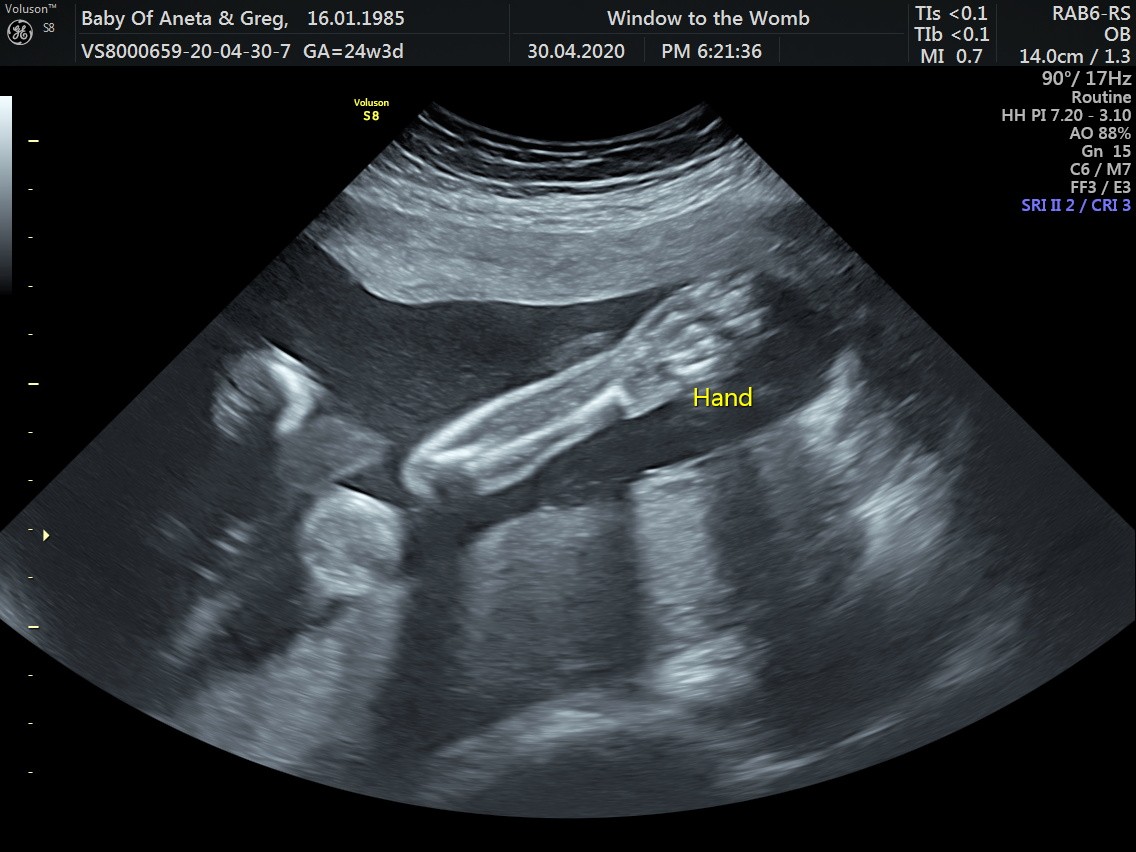

Wszystko z bejbikiem ok, wazy już 700g rozwija się według tego co powinien czyli dalej ma 24 tygodnie.

Łożysko poszło do góry, ale mięśniak rośnie. W miesiąc powiększył się o 3cm wiec ma już 7cm średnicy i całkowicie zasłania szyjkę. Ten ból który czuje to od ucisku przez mięśniaka.